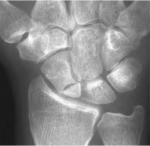

The scaphoid or navicular is an important bone in the wrist. There are 8 small bones arranged in 2 rows. The scaphoid is on the thumb side. When people fall with the wrist extended, one potential injury is fracture of the scaphoid. One of the difficulties can be diagnosis since the initial X-rays are sometimes normal.

Sometimes when the pain is in the area called the snuffbox, even with normal X-rays the wrist is splinted until repeat X-rays are done and a definitive diagnosis can be made.

Repeat X-rays are typically done 10-14 days after the injury. Usually, the combination of examination and X-rays can determine with certainty if there is a fracture. If there is still some question, the wrist is again X-rayed 2 weeks later or a bone scan (or MRI) is performed. Sometimes a CT is also useful.